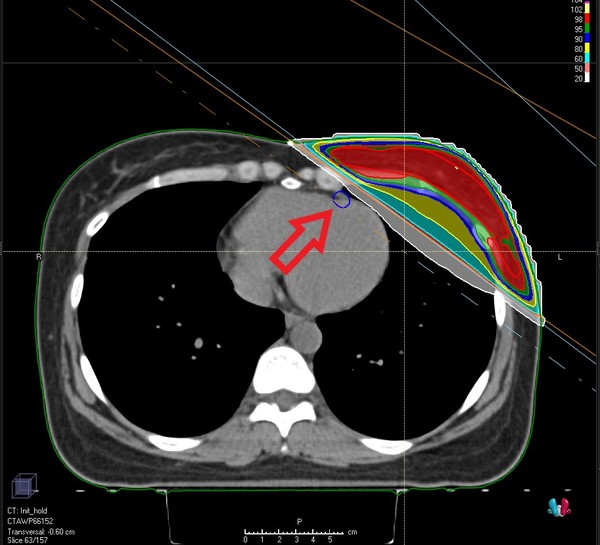

이에 한림대학교동탄성심병원 방사선종양학과에서는 왼쪽 유방 방사선치료 시 심장에 들어가는 방사선량을 최소화하기 위해 브레스홀딩(Breath Holding) 방사선치료를 시행하고 있다.

이 치료법은 왼쪽 유방에 방사선치료를 받는 환자에게 숨을 들이마신 채 이를 유지하면서 치료를 받게 하는 것이다. 숨을 들이마시면 폐가 부풀고 횡경막이 내려가면서 방사선 조사부위와 심장이 멀어지게 된다.

정확한 방사선 조사를 위해 비전RT사의 방사선치료 보조기기인 ‘Align RT’를 활용한 표면 유도 방사선치료 기법을 사용하고 있다. 사전 방사선모의치료 시 숨을 들이마시고 참은 상태로 CT를 촬영한 뒤 방사선치료를 설계한다. 이후 치료실에서 Align RT로 환자의 체표면의 움직임을 실시간으로 파악하며 방사선치료를 하는 것이다. 사전 CT촬영 시 환자의 체표면과 비교해 자세 오차가 큰 경우 자동으로 치료가 중단되며, 환자의 자세 오차는 0.1mm 단위까지 확인이 가능하다. 이러한 표면 유도 방사선치료 기법으로 환자가 숨을 참고 유지할 때의 정확한 위치와 각도를 계산한 뒤 심장을 피해 방사선을 조사할 수 있다.